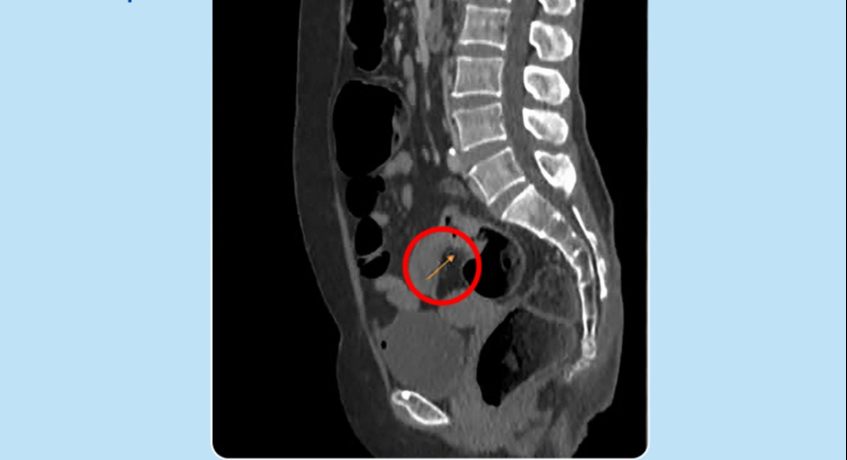

Tuy nhiên, sau khi thăm khám, kết quả nội soi trực tràng cho thấy, bà Phương bị u ở lòng trực tràng phát triển gây bán tắc, dạng vòng nhẫn, thâm nhiễm cứng. Kết quả MRI 3 tesla ghi nhận thành ruột dày không đều tại chỗ nối trực tràng với đại tràng sigma (12 mm), trên 30 mm không rõ cấu trúc, tổn thương dạng không nhầy chiếm hết chu vi, gây hẹp lòng đại tràng tại vị trí này.

Hình ảnh chụp MRI cho thấy khối u ở trực tràng (mũi tên vàng) của bà Phương. Ảnh: BVCC

Thạc sĩ, bác sĩ Ngô Hoàng Kiến Tâm, Trung tâm Nội soi và Phẫu thuật Nội soi Tiêu hóa cho biết người bệnh mắc ung thư trực tràng, trước đó có triệu chứng táo bón kéo dài mà không biết. Bác sĩ phẫu thuật cắt bỏ đoạn đại trực tràng chứa khối u đồng thời nạo vét hạch, ngăn ngừa khối u tiến triển gây chảy máu, tắc nghẽn đường tiêu hóa, tế bào ung thư có thể xâm lấn, di căn.

Trong quá trình phẫu thuật, bác sĩ quan sát chưa thấy nốt di căn, u trực tràng cao co kéo thanh mạc, u to khoảng 5 cm. Bác sĩ cắt ngang trực tràng dưới khối u 4 cm, tiếp đó đưa phần trên đại tràng cùng khối u ra ngoài qua đường mổ nhỏ dưới rốn, cắt ngang đại tràng cách bờ trên khối u 15 cm. Đoạn trực tràng lấy ra dài 25 cm. Sau khi kiểm tra với thuốc nhuộm huỳnh quang ICG cho thấy máu nuôi tốt, bác sĩ tiến hành nối đại tràng với trực tràng bằng máy.

Hậu phẫu, sức khỏe bà Phương hồi phục tốt, có thể đi lại và ăn thức ăn lỏng sau hai ngày, xuất viện sau 5 ngày. Kết quả giải phẫu bệnh là ung thư biểu mô tuyến xâm nhập thể thông thường biệt hóa vừa, giai đoạn 3A, 15 hạch được nạo vét ra ngoài không có tế bào u.